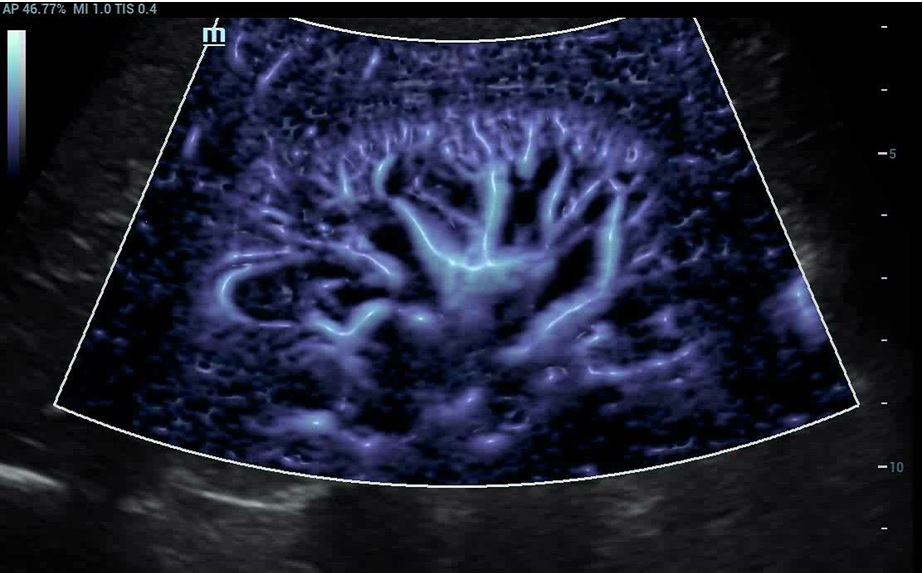

Glazing Flow : 3D zobrazenie ciev : Úplne nový spôsob zobrazenia prietoku krvi pomocou 3D vizualizácie

Glazing Flow : 3D zobrazenie ciev : Úplne nový spôsob zobrazenia prietoku krvi pomocou 3D vizualizácie

Glazing Flow : Nový spôsob demonštrácie prietoku krvi pomocou 3D vizualizácie. Špeciálne efekty nasnímaného svetla pri zobrazení rýchlosti prúdenia. K dispozícii s farebným a power dopplerom. Intuitívne a dynamické zobrazenie prietoku krvi vo vysokom rozlíšení a jasnosti, špeciálne pre tenké a prekrývajúce sa cievy.

Glazing Flow : Nový spôsob demonštrácie prietoku krvi pomocou 3D vizualizácie. Špeciálne efekty nasnímaného svetla pri zobrazení rýchlosti prúdenia. K dispozícii s farebným a power dopplerom. Intuitívne a dynamické zobrazenie prietoku krvi vo vysokom rozlíšení a jasnosti, špeciálne pre tenké a prekrývajúce sa cievy.